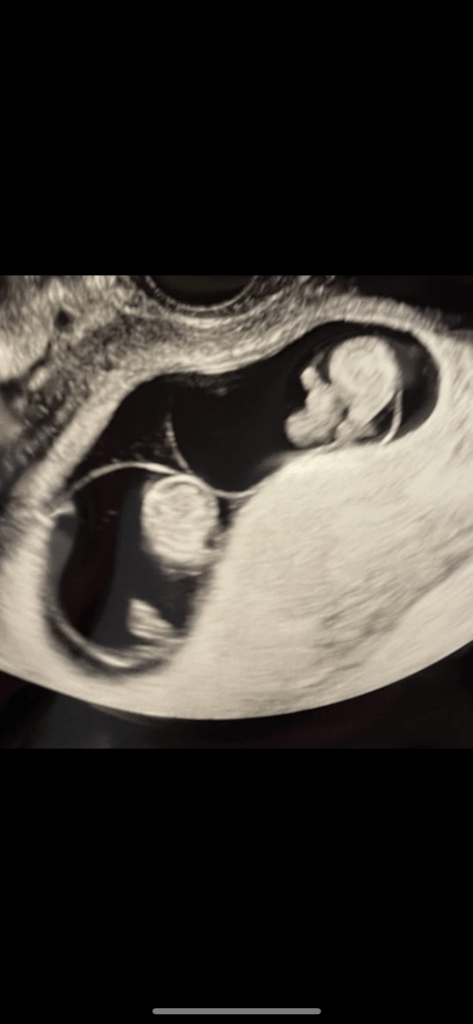

それは、妊娠4回目の健診でのことでした。エコーの画面には、しっかりと頭や手足が確認できる、小さな命の姿が映し出されていました。

その成長ぶりに感動していたスズキさんに、先生が問いかけます。「ん?わかった??」

「そうなんだけど…2人いるよ!」

「え?」――思わず声が出ました。それまで「赤ちゃんは一人」と聞かされていたスズキさんにとって、それはまさに青天の霹靂。驚きと同時に、どうしようもない不安が一気に押し寄せてきたと言います。